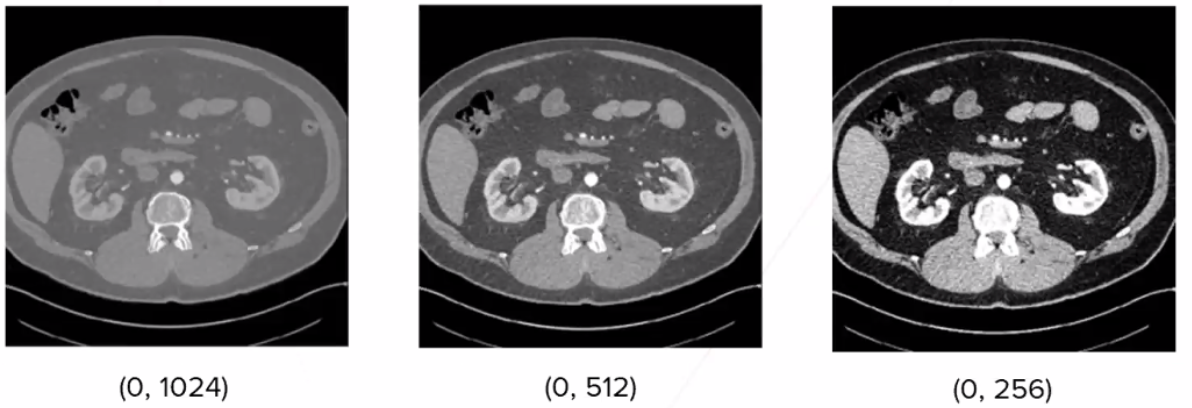

의료법등 여러 가지 문제로 의료 데이터는 고질적으로 적은량일 가능성이 큽니다. 기계마다 방사선의 차이에 따라 다름 Contrast Range를 가집니다. 이를 해결해주기 위해서 입력 채널을 여러 종류의 Contrast로 구성여 입력해주면, 그림과 같이 (0,12040)의 이미지와 (0,256)의 이미지는 매우 다른 사진임을 알 수 있습니다.